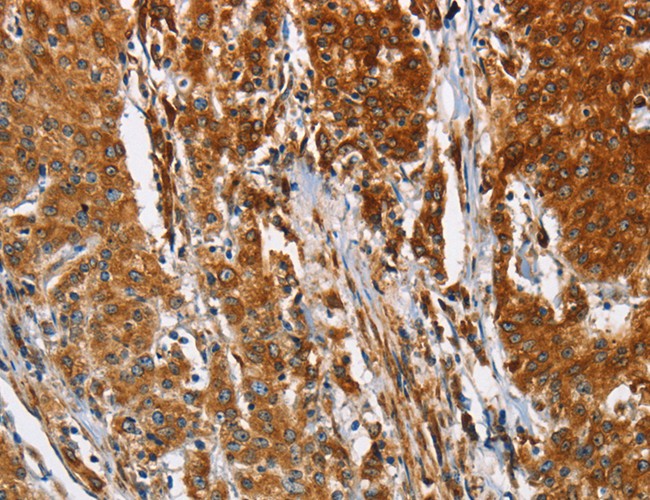

IHC (Immunohiostchemistry)

(Immunohistochemistry of paraffin-embedded Human gastic cancer using BCAP31 Polyclonal Antibody at dilution of 1:30)